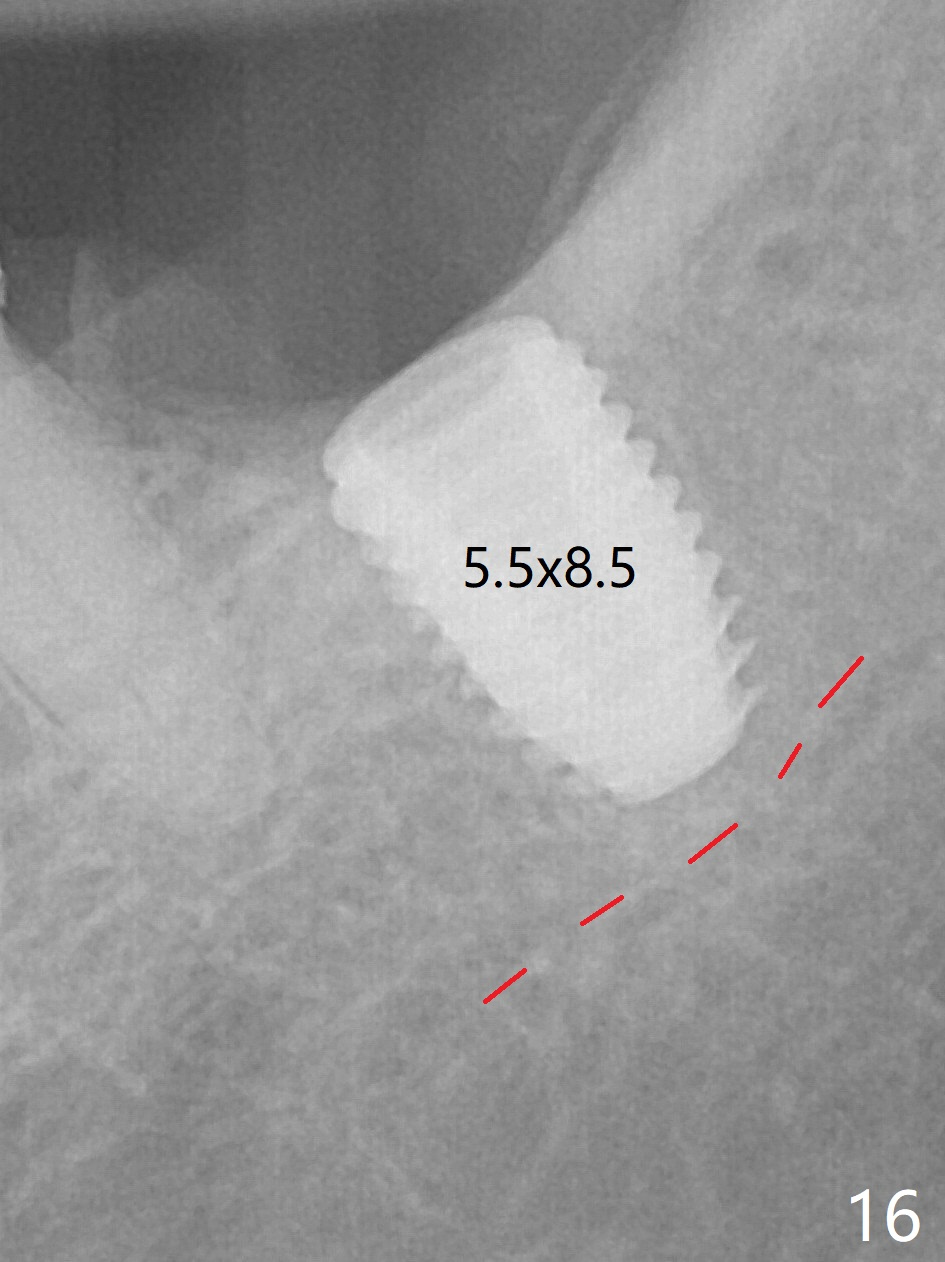

There is no apparent bone loss 4 months postop (Fig.10). There is chewing pain in spite of occlusal adjustment 7 months post cementation (Fig.11-13: increased radiolucency around the implant). The crown/abutment is removed and a healing abutment is placed (6x3 mm); the implant is stable. The patient return for re-evaluation in 3 months (15 months postop); radiolucency appears to reduce (Fig.14). But there is pain when the healing abutment is being removed. After local anesthesia, the implant is removed with a wrench. Following debridement of the osteototomy (intact, although tender), a 5x10 mm dummy implant with SLA surface is placed (Fig.15). After 5.5 mm tap, a 5.5x8.5 mm implant is placed with >50 Ncm (Fig.16). A 6.8x5 mm healing abutment is placed, followed by periodontal dressing. Re-analysis of preop CBCT shows that the bone density at the site is low: 70 units average. Progressive loading is necessary for this case 4-6 months postop. The soft and hard tissues around the implant seem to heal 4 months postop (Fig.17).